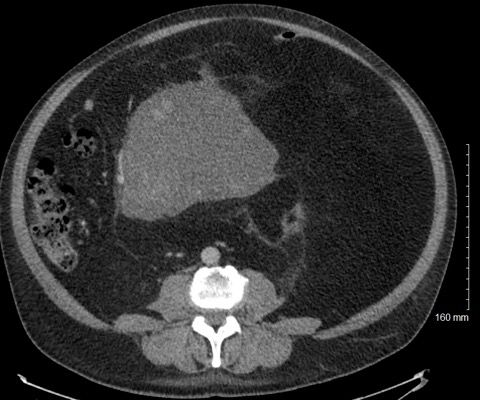

A 51-year-old man noticed abdominal swelling and distention with intermittent abdominal pain, early satiety, and decreased appetite over the past several months. A computed tomography scan of the abdomen is performed. What's your diagnosis?

A 51-year-old man noticed abdominal swelling and distention with intermittent abdominal pain, early satiety, and decreased appetite over the past several months. A computed tomography (CT) scan of the abdomen showed massive fat containing omental mass with a dominant solid component in the center (Figure A). After a CT guided biopsy (Figure B), he underwent surgical resection of this large retroperitoneal mass revealing a 33-pound macroscopic tumor (Figure C).

Based on the images shown, what is your diagnosis?